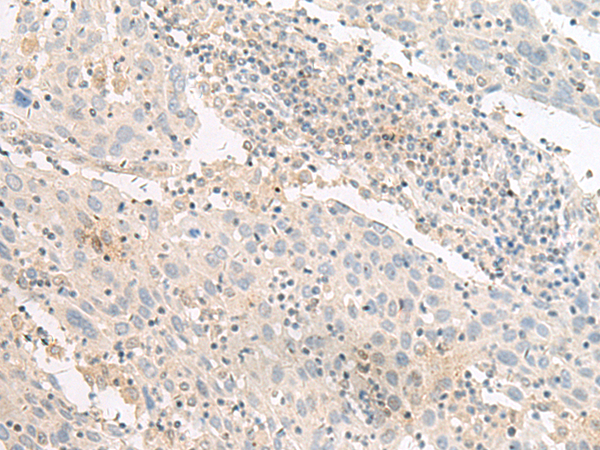

分类: 科研抗体货号: P13509别名: PSP24B; PSP24(beta)应用: IHC反应种属: Human, Mouse